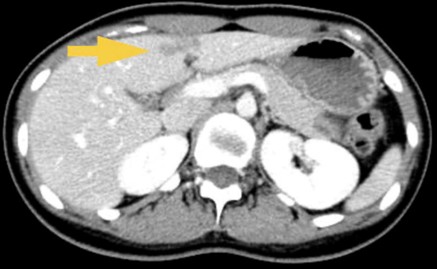

- Khối lớn vùng bẹn phải kích thước ~ 60x32mm, tỷ trọng hỗn hợp, ngấm thuốc sau tiêm, ôm quanh ~ 50% đường kính ĐM chậu ngoài kèm các hạch lân cận, hạch lớn kích thước ~ 14x8mm

Hình 2: Khối lớn vùng bẹn phải kích thước ~ 60x32mm, tỷ trọng hỗn hợp, ngấm thuốc sau tiêm,ôm quanh ~ 50% đường kính ĐM chậu ngoài ( mũi tên vàng)